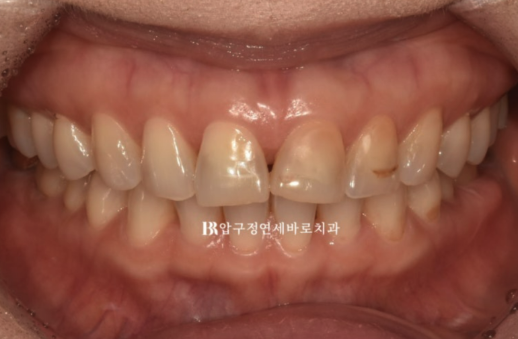

The very center shows a black triangle.

24.04

From a past orthodontic treatment experience, the front teeth are aligned, but the post-orthodontic maintenance was not done well, so the retainers have broken in several places.

The two front teeth are protruding forward from the dental arch.

This is the condition immediately after removal of the orthodontic appliance following 4 months of partial front-tooth orthodontic treatment.

The black triangle is gone, and the tilted tooth axis of the front teeth has improved.

24.08

The two protruding front teeth have also been moved back into place.